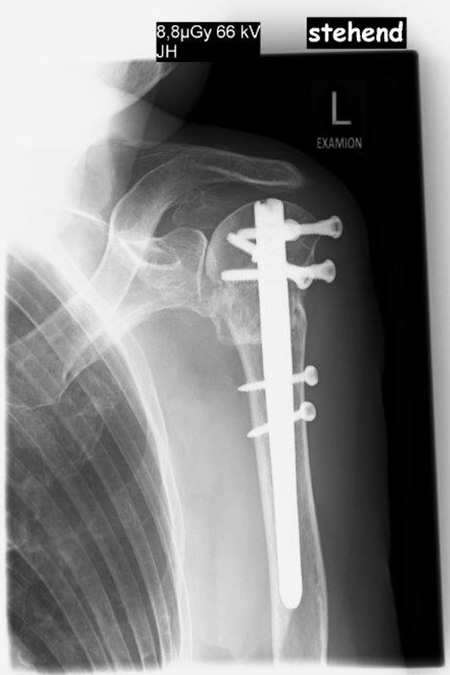

Bei der ersten Vorstellung klagte die 79 jährige Patientin über eine deutliche schmerzhafte linke Schulter und konnte diese kaum bewegen. Die Röntgenbilder zeigten einen fehlverheilten Bruch des Oberarmkopfes mit verschobenen Schrauben nach auswärtiger Nagelosteosynthese. Die operative Behandlung erfolgte mit einem inversen künstlichen Schultergelenk mit einem verlängerten zementfreien Schaft. Die erhebliche Vernarbung stellt eine besondere Herausforderung sowohl innerhalb der Operation als auch in der nachfolgenden Physiotherapie dar.

79 Jährige Patientin mit Oberarmkopffraktur und Plattenosteosynthese auswärtig versorgt stellt sich hier mit einem völligen Schultergelenksfunktionsverlust und Zusammenbruch des Oberarmknochens sowie Verschiebung bei liegender winkelstabiler Platte vor.

Es wurde die Platte entfernt und das Gelenk mit einer zementfreien Inversen Schultergelenksprothese nach Lösung der Verklebungen und Neufixierung der Sehnen wieder aufgebaut. 3,5 Monate nach operativer Versorgung sind die Sehnenansätze gut eingeheilt und eine ansprechende nahezu schmerzfreie Funktion erreicht.